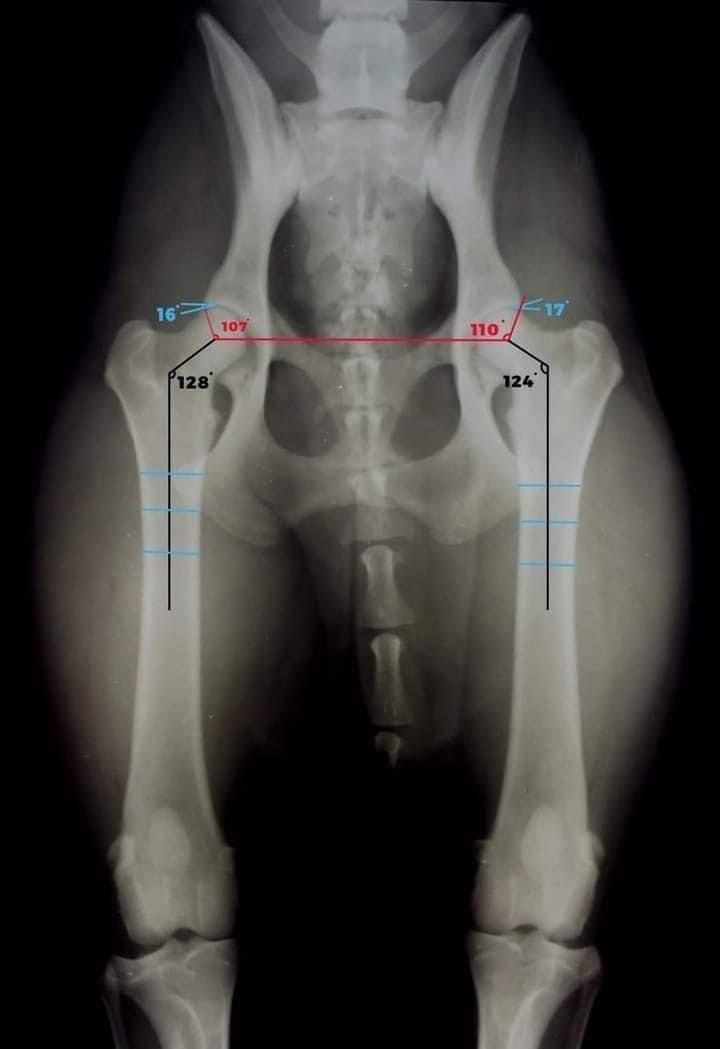

Дисплазия может быть установлена посредством рентгена или КТ (в определенных случаях). Для того, чтобы получить правильную картину, собака должна быть правильно разложена для рентгена.

Степени дисплазии ТБС бывают в Европе:

А, B, C, D, E,

А и В отсутсвие дисплазии. В дается тем собакам, у которых сустав не идеален на 1000%

С — самый легкий вариант дисплазии. При ней, сам сустав в порядке, но есть артроз или артрит небольшой.

Д — не в порядке сустав и есть сильный артрит и артроз. Собаки с Д в Европе не допускаются в разведение, в связи с тем, что процент генетики хоть и небольшой в дисплазии ТБС, но есть.

Е — сильнейшая дисплазия, то есть вертлужная впадина практически не развита и сильнейший артроз и артрит.

В Англии не используют буквы, потому что идеала, еще раз повторю, не существует. Минимум цифра естественно 0-0, (дается цифра на каждый сустав отдельно), но к примеру у Голден ретриверов, за всю историю, есть только одна собака, которая имела 0-0. Среднестатистическая цифра на Голденов в Англии на данный момент 19 на оба бедра. Собак до 19 используют в разведении без каких-либо ограничений. Но естественно, чем ниже сумма цифр — тем лучше. Все, что до 10 — это считается просто идеалом.

Дисплазия других суставов имеет полностью генетическое происхождение, во всяком случае на данный момент ветеринары всех стран сходятся в этом мнении.

Поэтому, лучше не использовать в разведении собак с диплазией к примеру локтей более, чем 1-1.